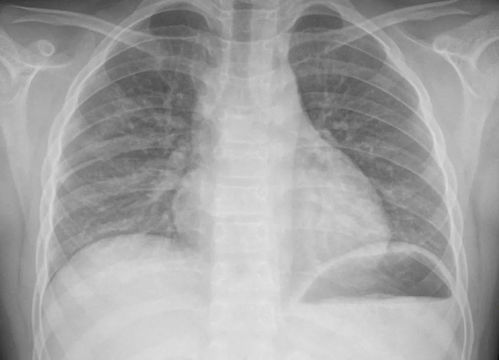

“白肺”并不是一个医学上的正式术语,而是对肺部影像学表现的一种形象描述,它通常指肺部在X光或CT扫描下呈现大片白色区域,提示肺部组织充血、水肿或实变,常见于重症肺炎、急性呼吸窘迫综合征(ARDS)等严重呼吸道疾病。